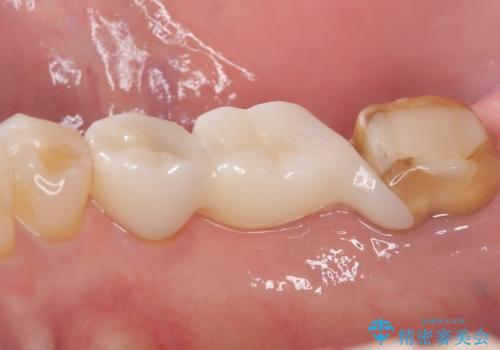

- 主訴:右下のセラミックのブリッジが何度も同じところで折れて壊れてしまう。

何度も右下6、7間でブリッジが折れてしまうとのことでした。対合歯とブリッジの連結部が強く当たりたわみやすい状態でした。破折しずらい金属を使用したブリッジの選択もありましたが、支台歯(右下7)が失活歯場合、破折リスクが高く、破折してしまった場合にまたブリッジを外しての再治療になってしまう可能性を説明したところ、全て単冠仕上げとできるインプラント治療を希望されました。